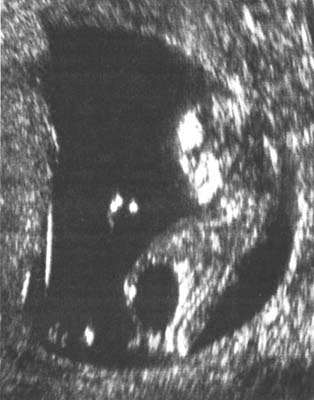

Rechercher une dilatation sous jacente de l’uretère (normalement non visible) : Urétéro-hydronéphrose.